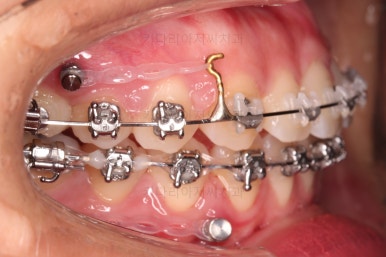

장치를 부착했는데요.

윗니는 웃을 때 더 많이 보이기 때문에 세라믹 장치를 선택하셨고, 아랫니는 거의 안보이는 타입이셔서 메탈장치로 부착을 했습니다.

위아래 둘 다 자가결찰 장치였고요.

동일 회사의 장치였으며 단지 재질만 메탈이냐 세라믹이냐의 차이가 있었던거죠.

이렇게 위아래는 설측이든 뭐든 메탈이든 세라믹이든 마음대로 섞을 수 있습니다.

아랫니는 앞니가 더이상 뒤로 들어가지 않도록 어금니를 앞으로 당기는 셋팅을 해줍니다.

그래서 위아래 좌우 모두 다른 용도로 미니스크류가 식립되었고요.

각각의 방향으로 계속 당겨줍니다.